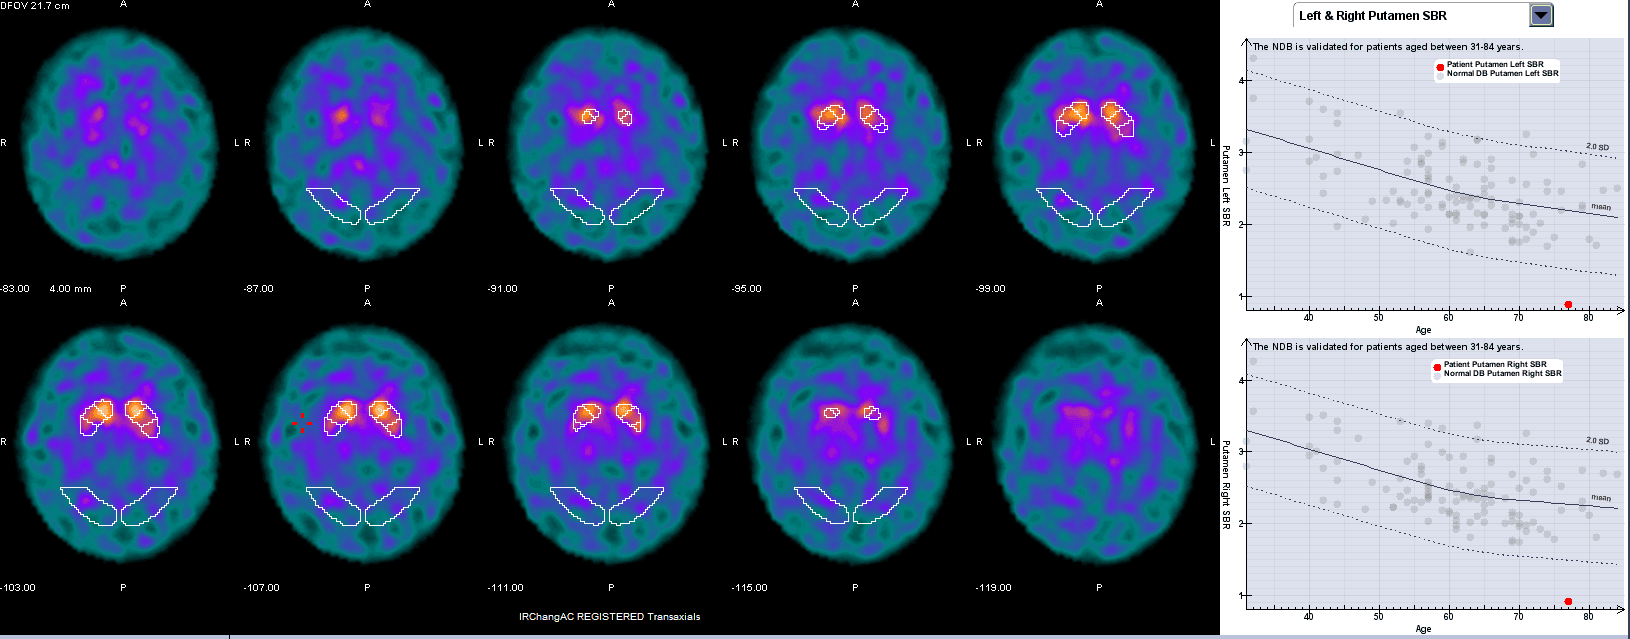

Snímkování se provádí za 3–6 hodin po aplikaci radiofarmaka, obvykle pomocí SPECT kamery. Výsledkem je obraz distribuce dopaminových transportérů ve striatu, který lze hodnotit vizuálně i kvantitativně.

Interpretace

Normální nález

- Symetrické vychytávání radiofarmaka ve striatu.

Patologický nález

- Snížení nebo absence vychytávání, typicky v putamen, s postupem i v caudatu.

- Častá je asymetrie odpovídající klinické lateralizaci příznaků.

- Pacient s třesem horní končetiny – klinicky nejasné, zda se jedná o Parkinsonovu nemoc nebo esenciální tremor. DaTScan ukazuje asymetrické snížení akumulace v putamen → potvrzuje neurodegenerativní parkinsonismus.